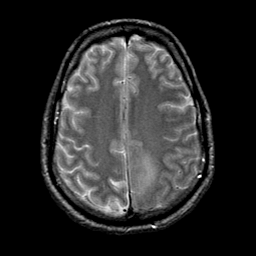

glioma overlay -- Slice #20

[Home][Help][Clinical] Slice 20